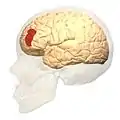

Image

Frontal view. Lateral view.

Lateral view.

Brodmann area 46, or BA46, is part of the frontal cortex in the human brain. It is between BA10 and BA45.

BA46 is known as middle frontal area 46. In the human brain it occupies approximately the middle third of the middle frontal gyrus and the most rostral portion of the inferior frontal gyrus. Brodmann area 46 roughly corresponds with the dorsolateral prefrontal cortex (DLPFC), although the borders of area 46 are based on cytoarchitecture rather than function. The DLPFC also encompasses part of granular frontal area 9, directly adjacent on the dorsal surface of the cortex.